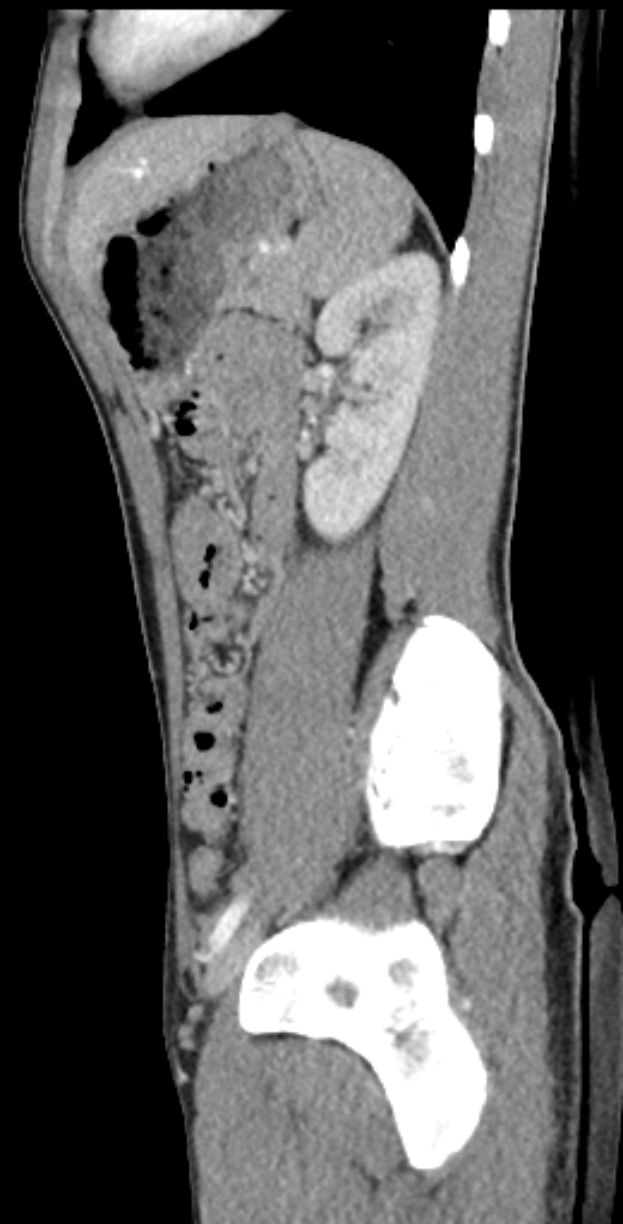

Eine MRT-Aufnahme eines Knies, die einen Riss in der Mitte zeigt, umgeben von einem dunklen Hintergrund.Isabella Reinhardt

Muskelverletzungen: Köln vorübergehend ohne Thielmann und Sebulonsen - Doppelschlag für den 1. FC Köln: Zwei Schlüsselspieler fallen verletzt aus

Der 1. FC Köln hat nach dem 2:2 gegen die TSG Hoffenheim zwei Leistungsträger mit Muskelverletzungen verloren. Sowohl Jan Thielmann als auch Sebastian Sebulonsen fallen aus und hinterlassen frühzeitige Lücken in der Startelf.